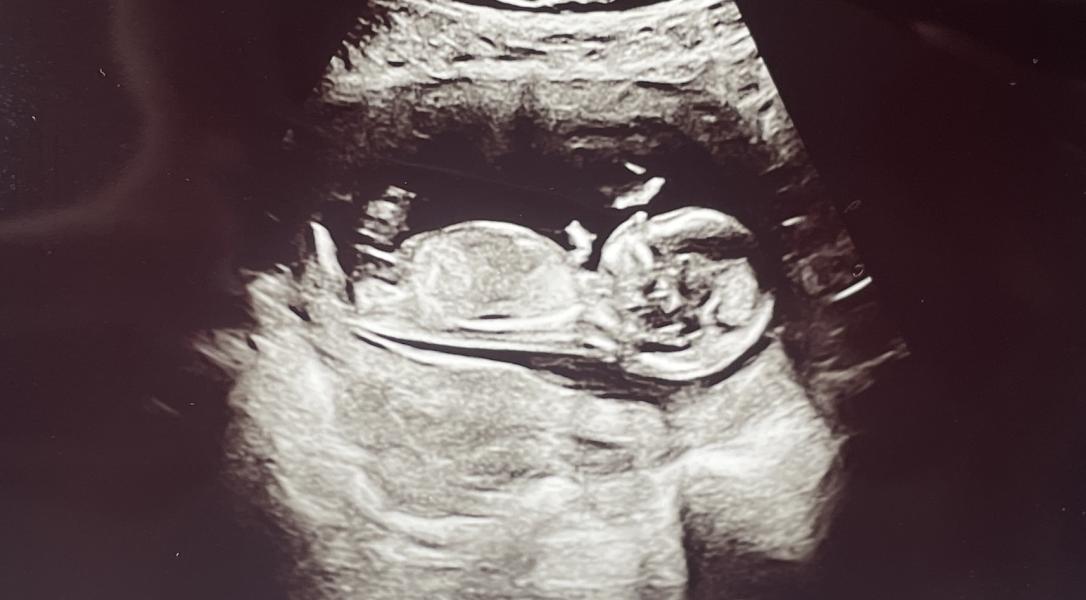

Девочки, кто разбирается в определении Пола на маленьких сроках, подскажите кого видите))) Как к человеку обращаться, он или она)))

Прошел первый скрининг, по узи все хорошо. Срок по узи опережает срок по месячным на 9 дней, 13 Нед и 3 дня поставили 😍

Кого видите, мальчика или девочку?

Врач сказала, что в первые секунды увидела мальчика. Потом, на протяжении всего узи, ей мерещилась девочка. Снизу тоже смотрела, но между ног Человек держал пуповину и все закрывал)))